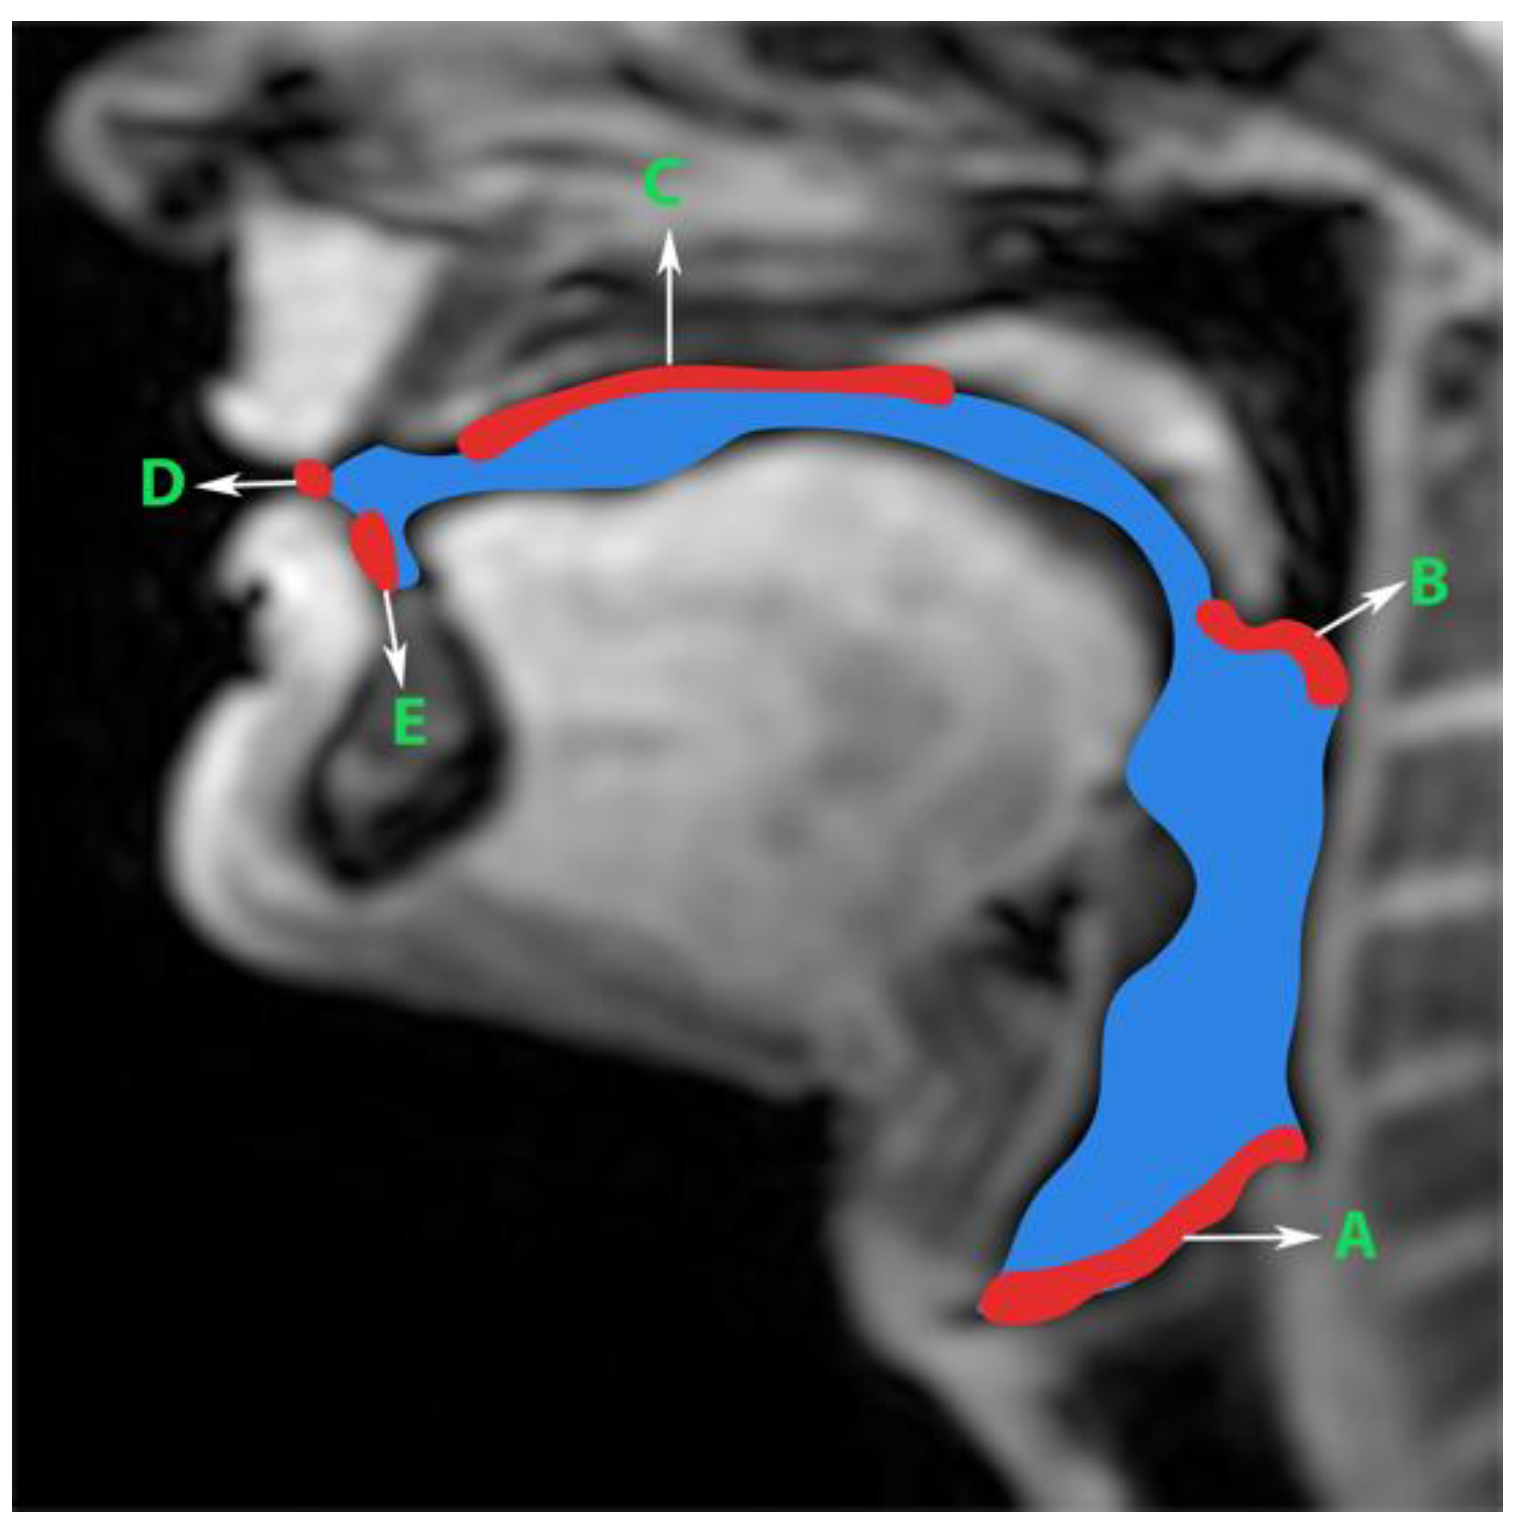

Figure 2. Prior to manual segmentation of the protocol speech MRI datasets, the anatomic boundaries of the vocal tract were established in consensus with all three human annotators: a vocologist, a radiologist, and a biomedical engineer. The blue colored region is the manually segmented upper airway. Red colored regions with notations show the boundaries for creating the manual segmentation. The boundaries are; A—lower boundary (vertebral column 6 and vocal fold), B—inferior boundary of velum, C—hard palate, D—a straight line connecting posterior edge of lower lip with upper lip, and E—region containing teeth up to the soft tissue connecting it.

Generation of manual segmentations: To train, validate, and test the STL UNET, we leveraged human annotators to generate manual segmentations. To reduce the subjectivity of test labels, each image in the test set was segmented by three expert humans. The first human annotator was a radiologist with expertise in body, cardiovascular, and thoracic imaging, and with more than 10 years of experience in radiology (author: Priya). The second human annotator was a professional voice user, researcher, and vocologist with more than 20 years of experience in human vocal tract anatomy and voice research (author: Meyer). The third annotator was a graduate student with 4 years of experience in upper-airway MRI and image processing (author: Erattakulangara). Prior to segmentation, all three users established and agreed to an anatomical guide and landmarks to segment the vocal tract (see Figure 2). The three users listed above manually annotated the test set in each of the three protocols by manual pixel-wise labeling of tongue, velum, and airway in either MATLAB R2021 (Mathworks, Natick, MA, USA) or the Slicer platforms (https://www.slicer.org) accessed on 4 August 2022. The third user alone annotated the images in the training and validation sets.